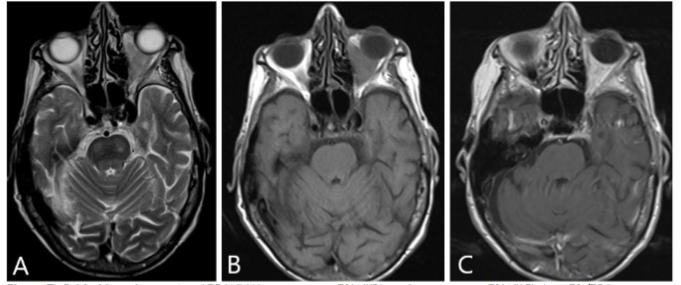

Orbital MRI provided a clearer characterization of diffuse retro-orbital soft tissue thickening, involving the fat, extraocular muscles, and lacrimal glands, leading to pronounced right orbital proptosis and globe eversion. The right globe was flattened with optic nerve stretching. The retrobulbar mass extended posteriorly into the orbital apex without cavernous sinus involvement, and there was also further extension into the lateral face, affecting the temporalis muscle.

FDG PET/MRI was used to characterize the extent of the disease and determine the optimal site for tissue biopsy. FDG PET/MRI revealed multiple markedly FDG-avid cervical lymph nodes, focal intense uptake in the right parotid region, and focal uptake in the right orbital infiltrative mass with maximum Standardized Uptake Value (SUV) of 13. Guided by FDG PET/MRI, the patient underwent a biopsy of the most FDG-avid region of the right orbital mass, which was diagnosed as necrobiotic xanthogranuloma with increased IgG4 expression. The patient was treated with cyclophosphamide, corticosteroid, and high-dose IVIG followed by bone marrow stem cell transplantation and showed a good response in terms of both imaging and clinical evaluation. The genetic and histopathologic findings of this case are discussed in detail by Guess et al.

IgG4-RD is a systemic inflammatory condition of unclear origin marked by the infiltration of tissues by IgG4-positive plasma cells and the presence of sclerosing inflammation. Orbital involvement can be observed in up to 40% of cases, with proptosis and periorbital edema being the most common clinical presentations. Pain is reported in approximately 7% of these patients. Imaging of IgG4-related orbitopathy typically reveals an infiltrative retro-orbital mass, primarily involving the extraocular muscles, with the lateral rectus being most commonly affected. Notably, the anterior tendons are spared in the majority of cases. It is often accompanied by lacrimal gland involvement and paranasal mucosal thickening.

Nonspecific orbital inflammatory syndrome (NSOIS), formerly known as orbital pseudotumor, is another differential diagnosis to be considered in this patient, although it is uncommon in the pediatric population. NSOIS can affect various orbital structures, including the extraocular muscles, retrobulbar fat, optic nerves, and globe. The extraocular muscles are the most frequently involved muscles, with characteristic involvement of the musculotendinous insertions. The clinical presentations typically include bilateral proptosis, painful ophthalmoplegia, and diplopia. CT and MRI findings differ based on the disease’s location but typically reveal thickening of the extraocular muscles, including musculotendinous insertion, enlargement of the lacrimal gland with surrounding inflammatory changes, and a thickened, enhancing sclera.